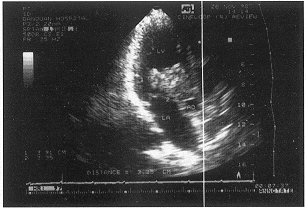

左室流出道粘液瘤致主动脉阻塞1例

李元玲 张启萍(200065 上海铁道大学附属甘泉医院心超室);王永武 曹克坚(胸外科)

患者男性 ......